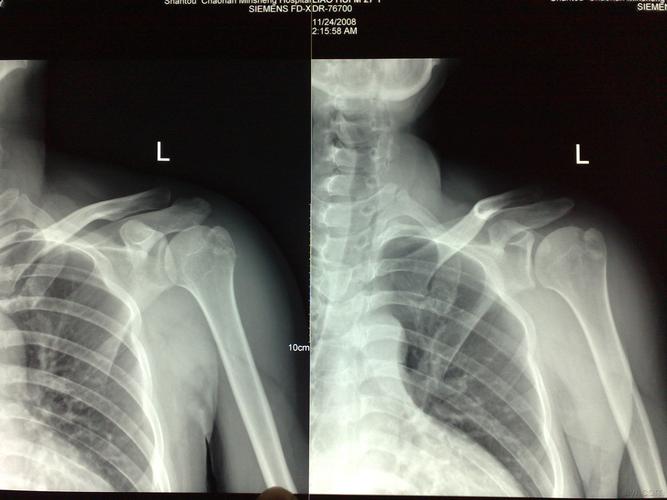

儿童肩关节x线

儿童肩关节x光片

儿童肩关节x线图片